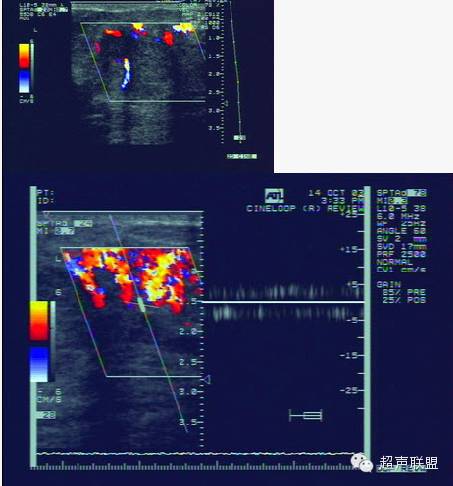

5.多普勒灵敏度和功率多普勒技术的改善,使观察乳腺内部的血管分布更为直接。在20世纪80年代初多普勒超声技术刚用于血管检测时,主要采用连续波多普勒,因为它有较高的灵敏度。乳腺肿块周围的血管内含有较高的血流速度被认为是恶性肿瘤的象征。现在,只需用彩色多普勒观察分布于肿块内外的血管数量即可作出同样的诊断。尽管对于多普勒信息的解释仍有异议,但多数研究者及ATL/FDA临床实验的结果确认了乳腺肿块中增加的血管分布预示了恶性肿瘤。

使用造影剂的缺点在于造价高,并需要静脉注射。而且,灵敏度更高的多普勒仪器的出现使得血流信号的增强已不像过去那么重要。图4显示,在移植入肝脏中的实验性肿块上运用造影剂后,组织的对比度增强。类似的增强是否也适用于乳腺组织亟待研究。